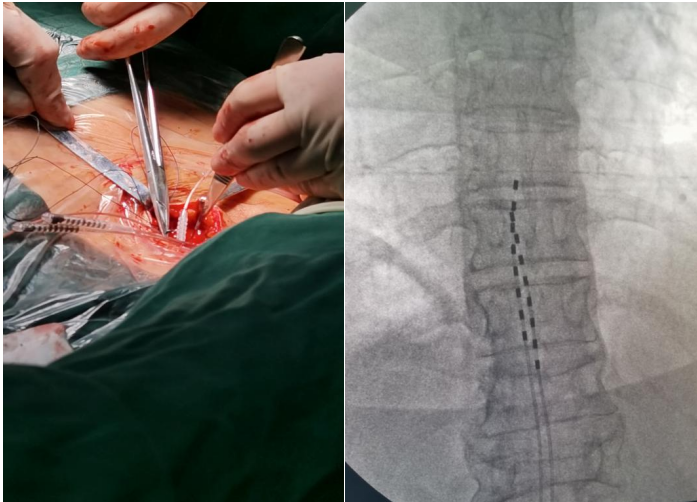

▲ 电极植入

测试期手术于2022年12月中旬进行。

▲ 术中观察